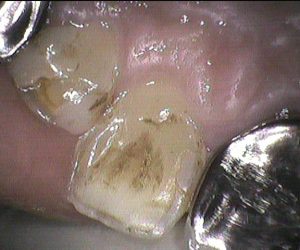

今日のクリーニングです。 クリーニング前 後 クリーニング前 後 半年に一度くらいの頻度で定期的にクリーニングに来てくださっている患者さんです。 綺麗に磨けていて、 […]